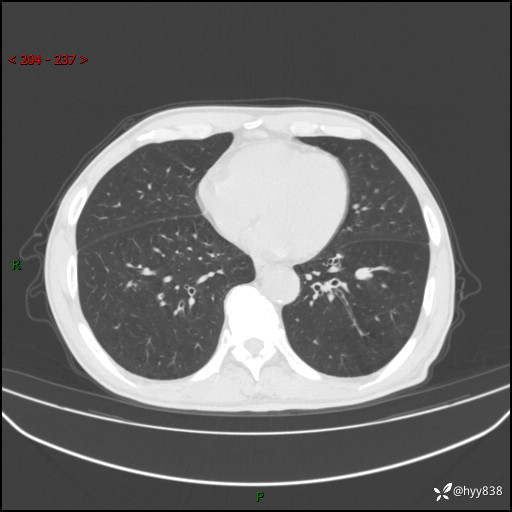

辅助检查:CT

胸部CT平扫

增强动脉期+静脉期

各期CT值:38Hu 52hu 55hu